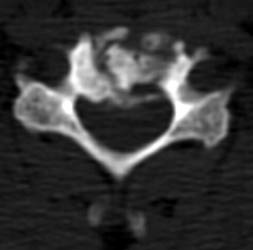

The axial images, and the sagittal reconstructions (not

shown) show some central lucency in the region of graft placement,

suggesting partial resorption of the graft material. |